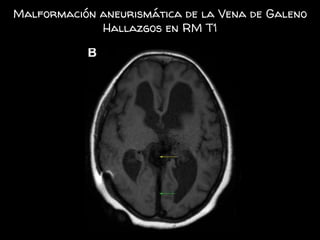

RMN DE CRÁNEO

20/06/2023

ADQUISICIÓN AXIAL

T1 T2 FLAIR

DWI ADC EG

ADQUISICIÓN AXIAL.

T1 CC

ANGIO TOF

 Malformación arterio-venosa cerebral con

dilatación aneurismática de la vena de galeno vs

aneurisma de la vena de galeno vs fístula

arteriovenosa pial. Escala de Spetzler – Martin 5

puntos.

 Pansinusopatía.

 Hipertrofia turbinal.

CONCLUSIONES: